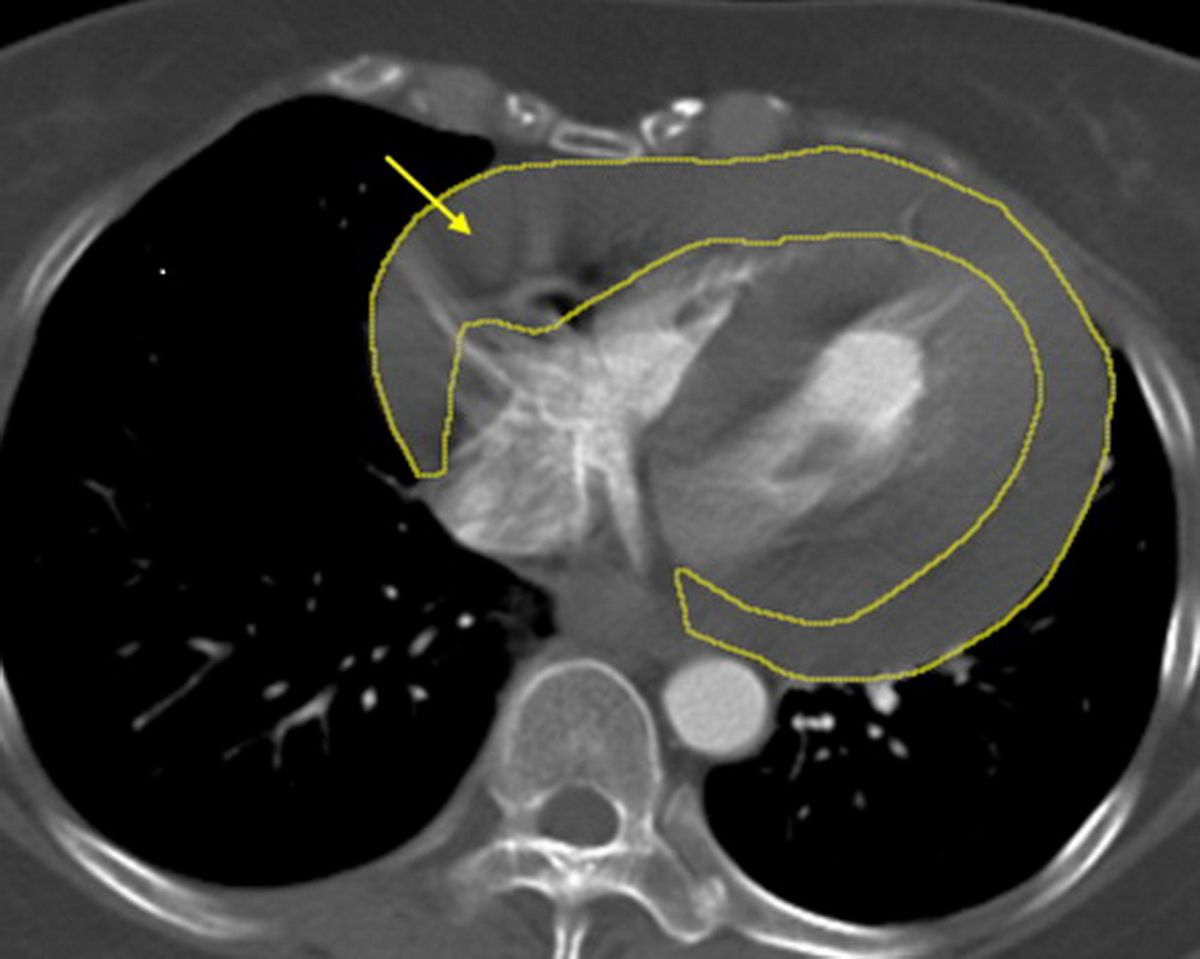

土城長庚醫院胸腔及心臟血管外科主治醫師鄭元熙表示,心包積血是指血液在短時間內大量累積於心臟外層,造成心臟受壓,無法正常舒張與跳動,血壓會迅速下降,甚至在數分鐘內引發心跳停止,屬於典型的立即致命急症;而升主動脈是全身最粗大的血管,一旦剝離或破裂,出血速度極快,死亡率極高,臨床上不乏患者尚未送醫即發生致命後果。

陳小姐回憶,自己長期有反覆頭暈情形,過去曾因頭暈騎車摔倒,但症狀短暫而未進一步就醫;此次休克後,影像檢查確認為大量心包積血,醫療團隊第一時間成立跨科搶救小組,由心臟外科緊急執行「劍突下心包開窗術」,迅速解除心臟壓迫、穩定循環,隨後由血管外科無縫接軌完成高難度的「升主動脈置換術」,以人工血管重建破裂血管。